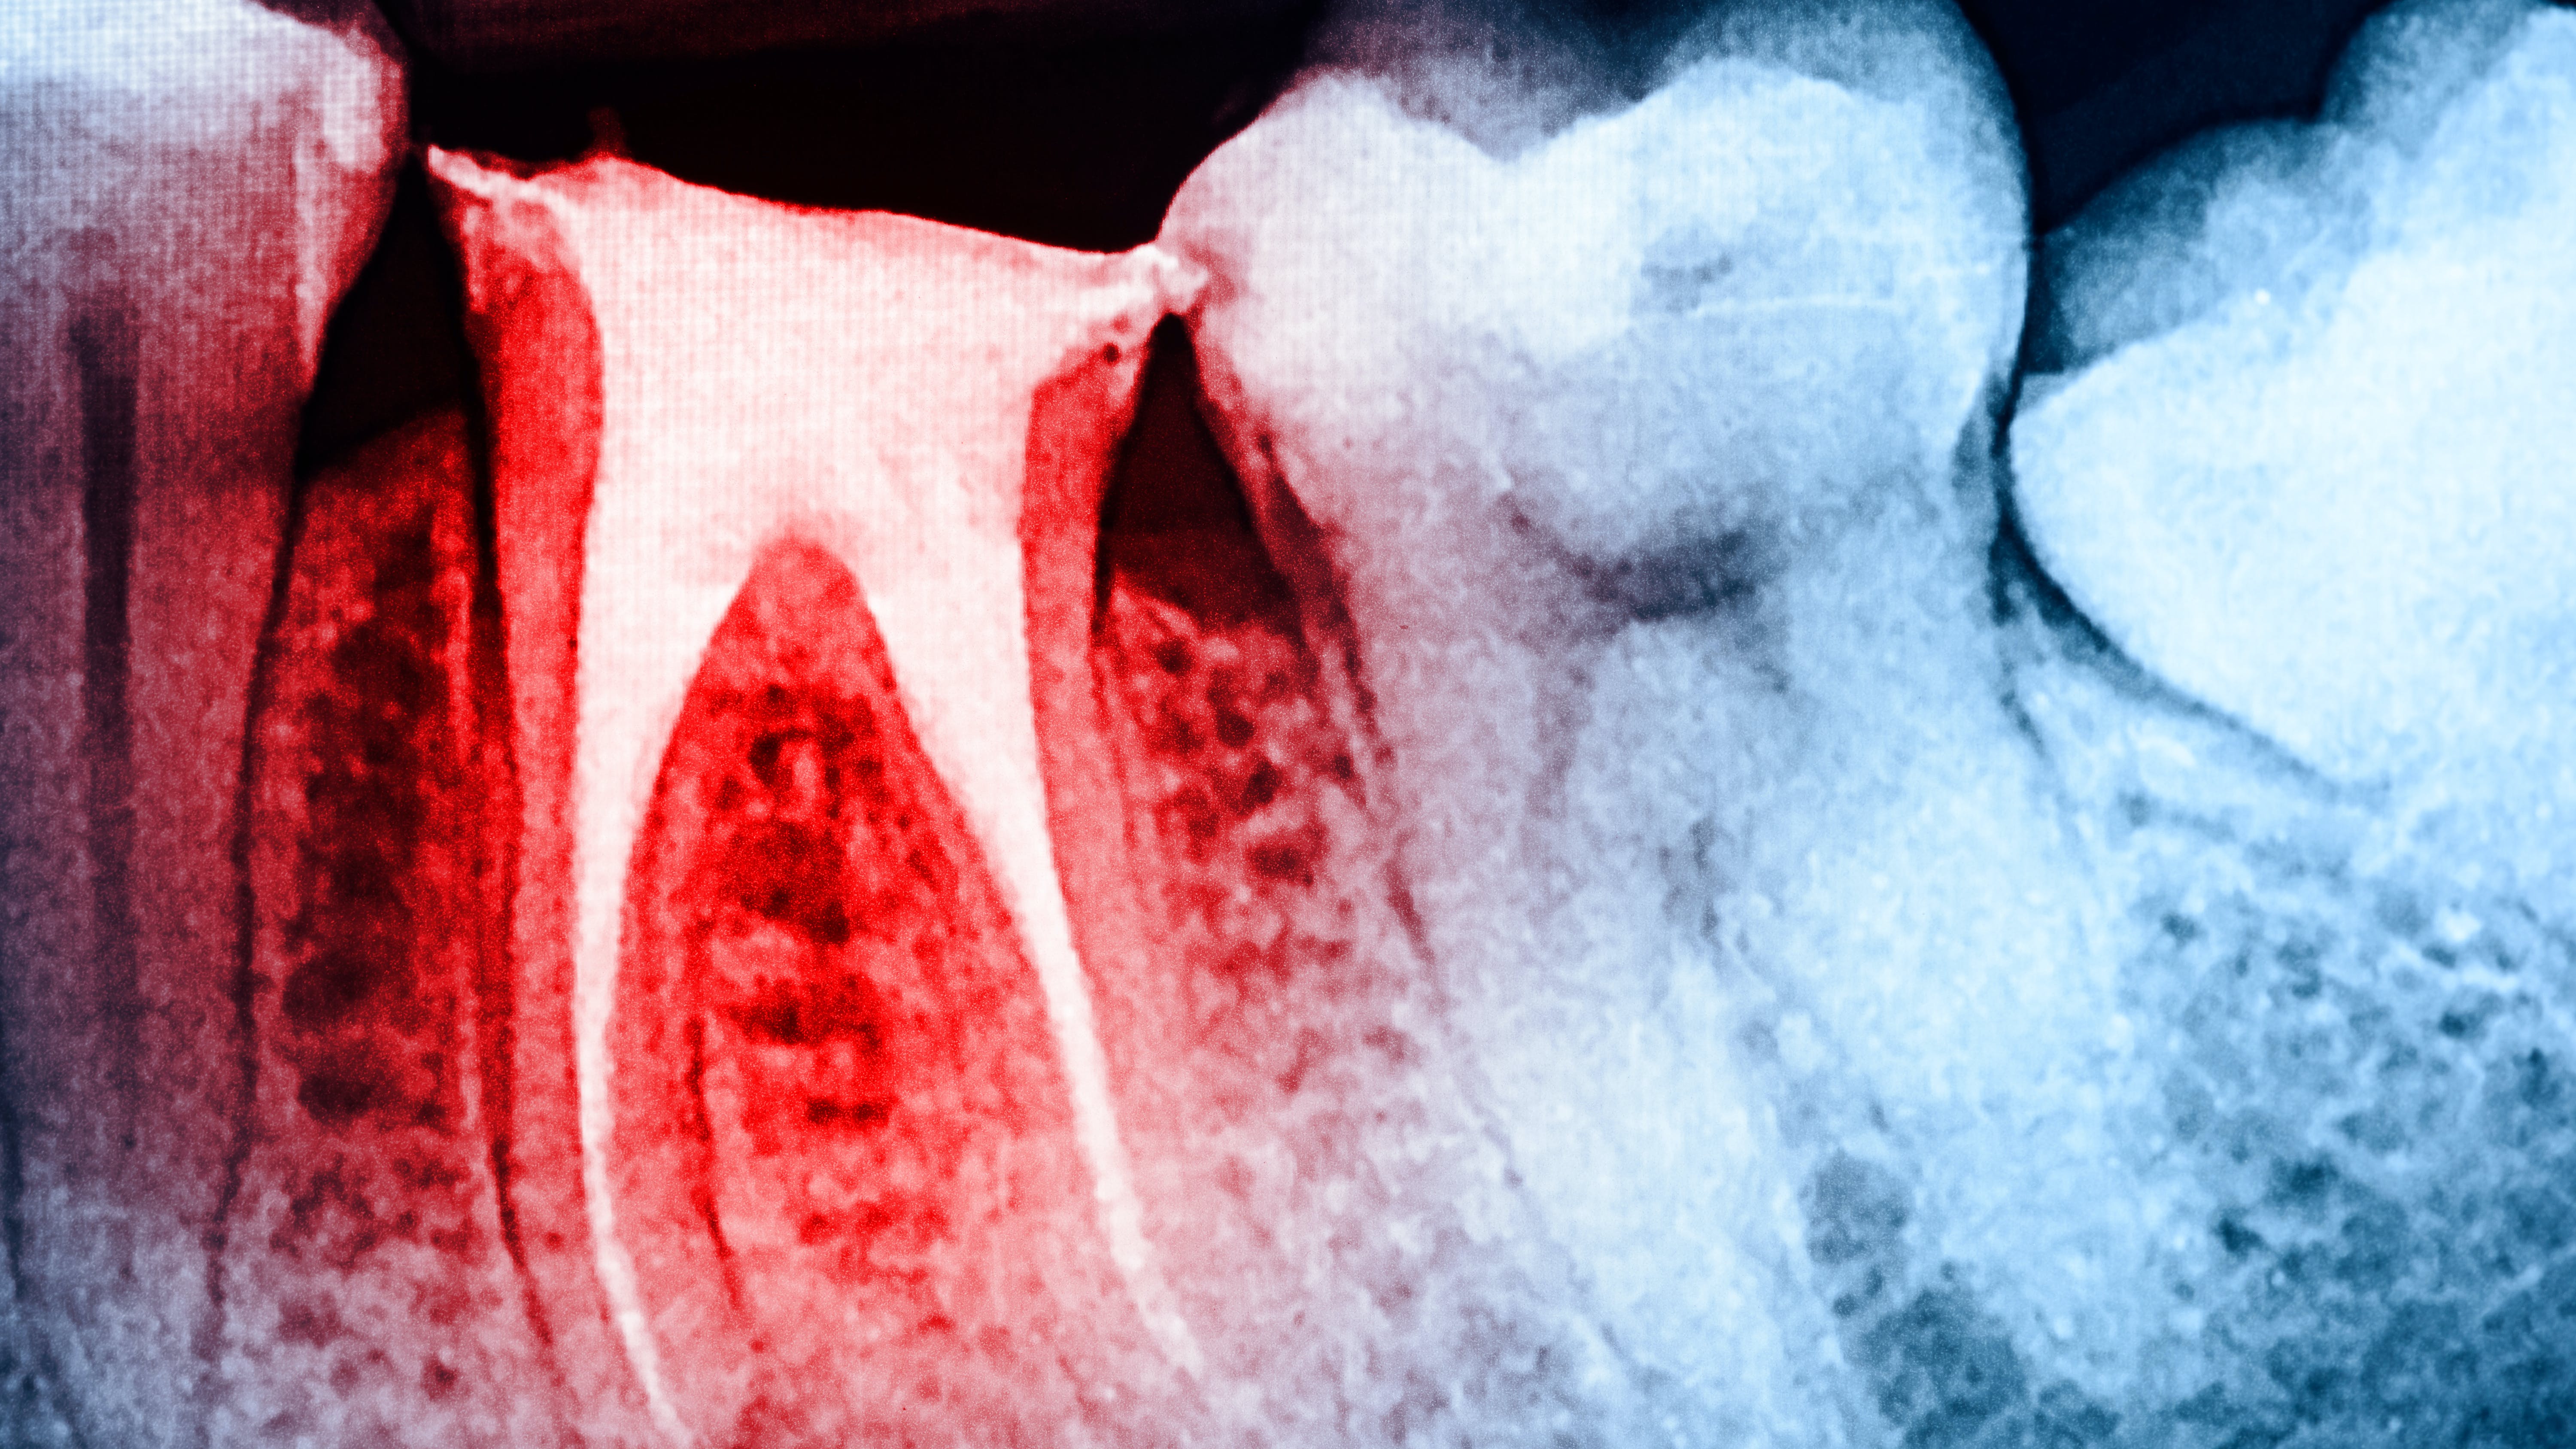

The periodontium surrounding the tooth can be a source of pain, especially if there is a concurrent periodontal lesion along with an endodontic lesion (figure 3). The tooth should be clinically examined and radiographs taken following root canal treatment to evaluate both hard and soft tissue. Hard-tissue defects, such as intrabony defects and furcation involvement, can cause inflammation leading to tooth pain. In addition, soft-tissue recession can expose root surfaces, which can then lead to sensitivity and tooth pain. Food impaction, especially if the tooth is temporized, can also mimic tooth pain. Gingival irritation from the rubber dam clamp used during the root canal can simulate tooth pain, but it is usually temporary and can be alleviated with rinses or medicaments. Referral to a periodontist may be required for pain of periodontal origin.